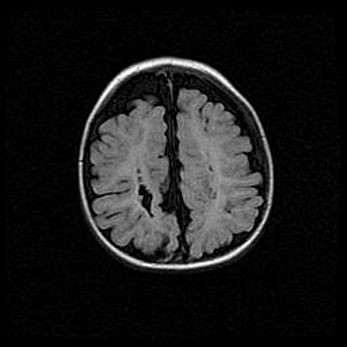

Лейкомаляция с кистозно-глиозной дегенерацией головного мозга.

Возраст: 2 месяца 25 дней

Вес: 6400 г

Окружность головы: 40 см

Срок гестации: 41 неделя

Лейкомаляцию относят к ишемически-гипоксическим повреждениям головного мозга, диагностируемым у новорожденных. При лейкомаляции в головном мозге обнаруживают очаги некроза, возникшие после тяжелой гипоксии и нарушения кровотока. В процессе морфогенеза очаги проходят три стадии: 1) развития некроза, 2) резорбции и 3) формирования глиозного рубца или кисты. Перивентрикулярная лейкомаляция (ПЛ) встречается примерно в 12% случаев среди новорожденных, обычно – у недоношенных детей, причем, частота ее зависит от массы, с которой младенец появился на свет. Наибольшее число малышей страдает лейкомаляцией, если масса при рождении 1500-2500 г.